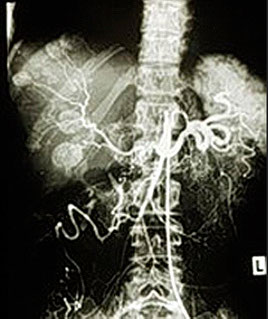

Abb.1: Angiokatheter im Truncus coeliacus zur regionalen Chemotherapie von Lebermetastasen eines Dünndarmkarzinoids. Diese Metastasen sind so gut vaskularisiert, dass sie sich mit dem arteriell applizierten Kontrastmittel darstellen lassen.